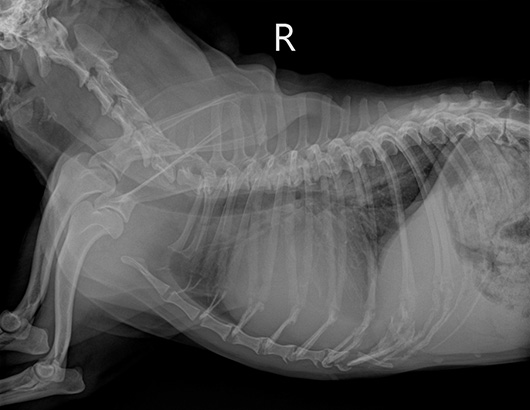

正常犬のレントゲン